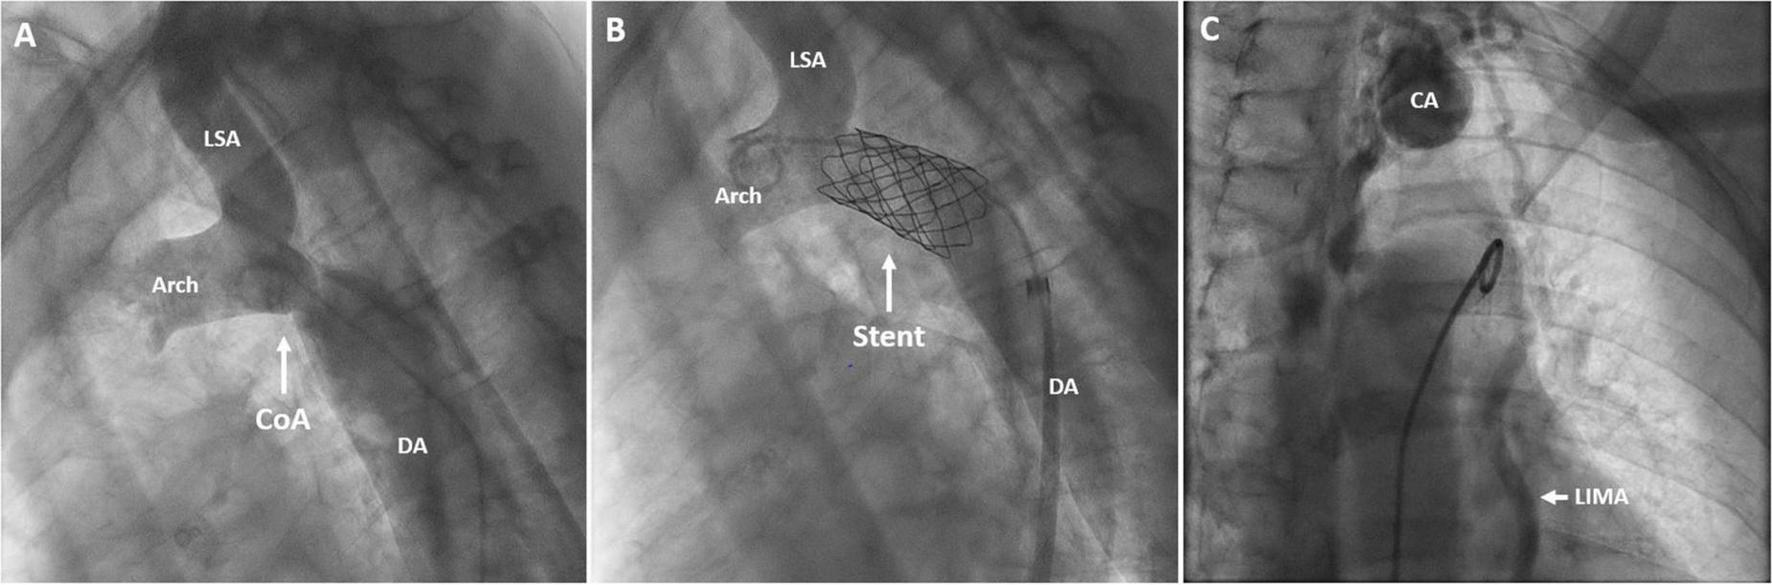

FIGURE 4

Angiography of the aortic arch and descending aorta before (A) and after stent implantation (B). Angiography of the collateral artery aneurysm (C). DA, descending aorta; CoA, coarctation of the aorta; Stent, covered stent in the coarctation zone; CA, collateral aneurysm; LSA, left subclavian artery; LIMA, left internal mammary artery; Arch, aortic arch.

A three-dimensional (3D) print of the heart, aorta, and collateral vessels, including the aneurysm, was constructed to facilitate a better understanding of the complex anatomy. The patient was discussed in the adult congenital heart team; considering the patient’s age and the perioperative risk of aortic surgery in the presence of extensive and aneurysmatic collaterals, we pursued a primarily percutaneous strategy. Invasive pressure measurements revealed systolic blood pressures proximal and distal to the CoA of 178 and 95 mmHg, respectively. This resulted in a gradient of 83 mmHg, warranting the indication for intervention. To treat the coarctation, a covered stent was implanted (Figures 4A, B) with good angiographic results and alleviation of the pressure gradient. Figure 4C shows the angiography of the collateral artery aneurysm that was subjected to conservative treatment. Coronary angiography confirmed a significant stenotic lesion in the proximal left anterior descending artery (80–90% stenosis), for which a percutaneous coronary intervention (PCI) with stent implantation was performed. The other coronary arteries showed non-significant atherosclerotic lesions. The post-operative period was uneventful, dual antiplatelet therapy with acetylsalicylic acid and clopidogrel was started, and amlodipine was discontinued. Two months later, losartan was discontinued due to the normalization of blood pressures to 100–125/70 mmHg.